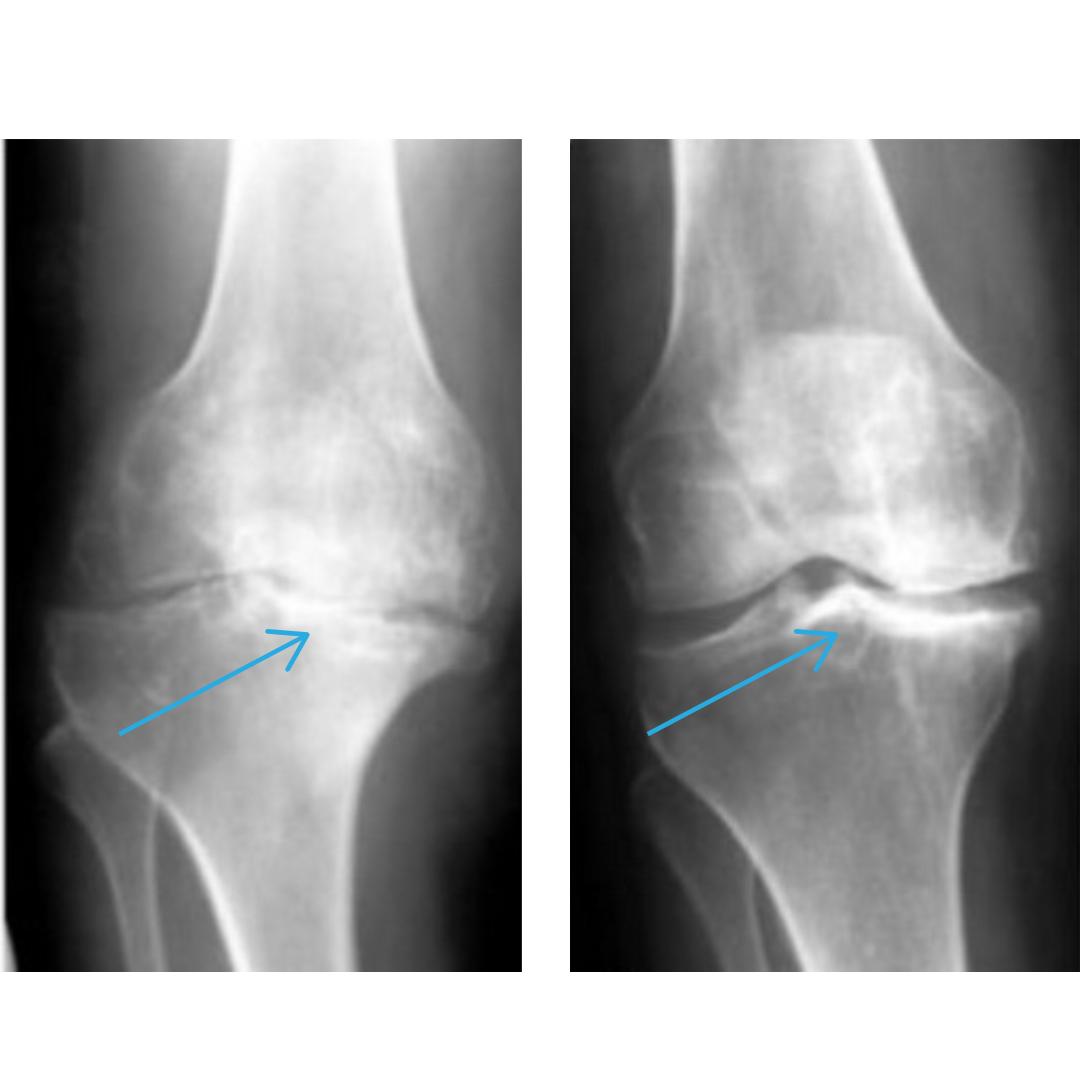

Друзі, хочу поділитися своїм досвідом, бо, можливо, комусь це теж допоможе. Близько двох років я страждав від нестерпних болів у спині. Діагноз - грижа L5-S1, екструзія до 8 мм. Хто стикався, той розуміє, що це за біль: простріли в попереку, оніміння ноги, не міг довго стояти чи сидіти, ночами не спав. Лікарі пропонували операцію, але я боявся ускладнень. Перепробував усе - уколи, блокади, масажі, мазі. Ефект був, але короткий. Болі поверталися знову. Одного дня натрапив в інтернеті на інформацію про натуральний засіб для відновлення хрящів і дисків. Чесно спочатку не повірив. Але, коли почитав про клінічні результати й відгуки людей, які позбулися гриж без операцій, вирішив спробувати. І не пожалів! Уже через 10 днів відчув, що біль стихає, спина перестала “стріляти”. Почав нормально спати, вставати без болю. Через місяць пройшов повторне МРТ - грижа з 8 мм зменшилася до 3,8 мм! Ось знімки до і після курсу. Зараз живу без болю, можу ходити, працювати, нахилятись, як раніше. Повернувся до повноцінного життя. Якби мені хтось раніше сказав, що можна обійтись без операції не повірив би. Але тепер я переконаний: відновити спину реально!

Натрапила на цей метод зовсім випадково, коли шукала щось ефективне для чоловіка він вже кілька років страждав від болю в коліні. Постійні обмеження в русі, набряки, іноді навіть вночі не міг нормально спати. 😞 Після курсу цього методу результат перевершив усі очікування! На знімках чітко видно різницю суглоб став рухливішим, біль зник, і він нарешті повернувся до нормального життя без операцій та уколів. Рекомендую всім, хто зіштовхнувся з подібною проблемою! Не тягніть, як ми, бо здоров’я - найцінніше в такий важкий час🙏